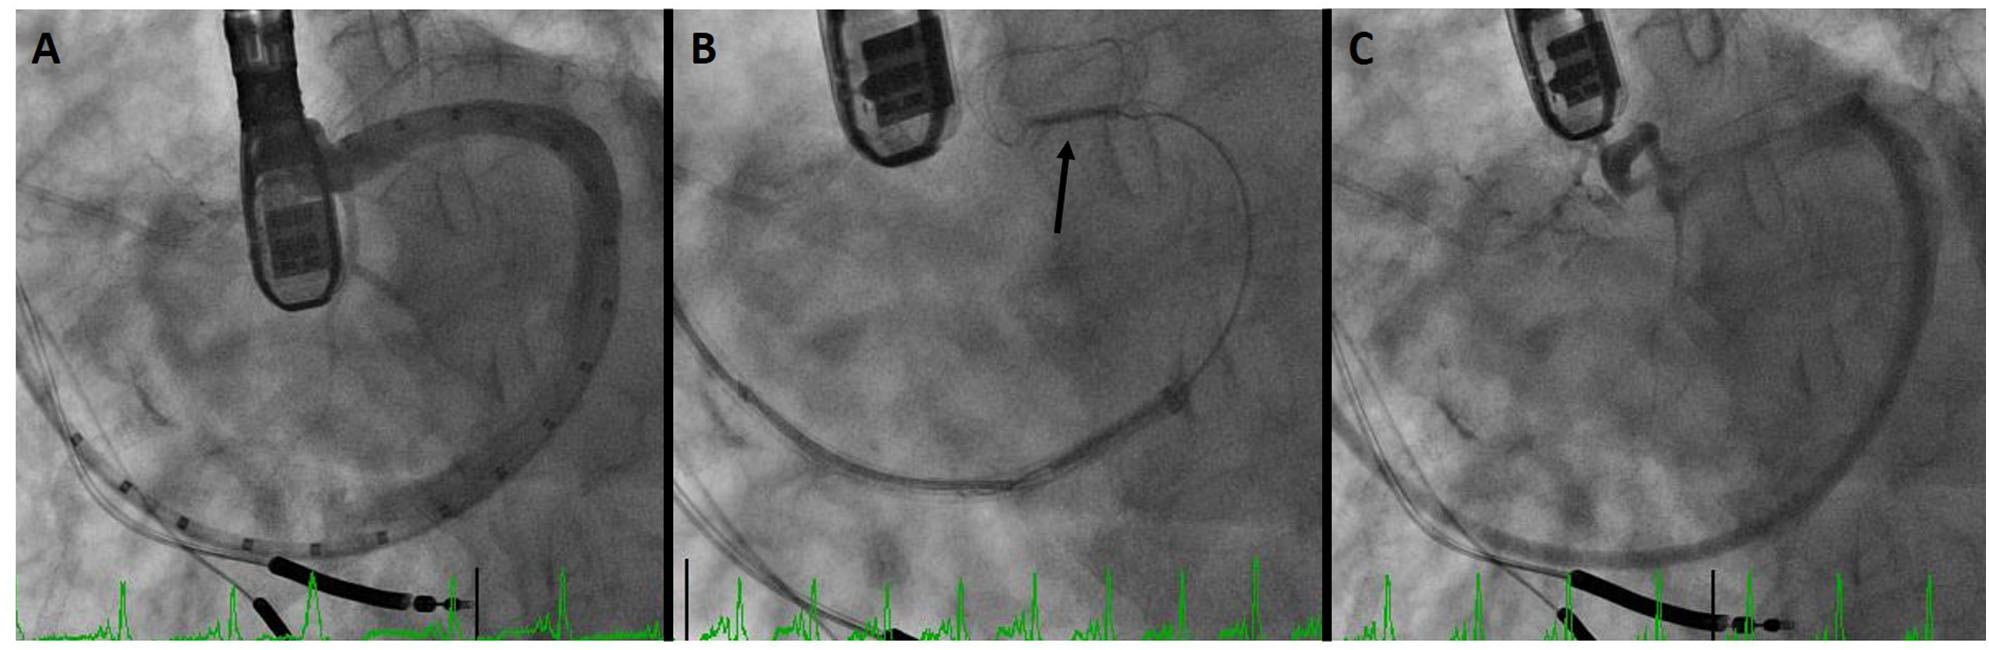

Figure 3 demonstrates a CS dissection in a patient who presented for Carillon implantation. Due to impingement of the circumflex coronary artery by the distal anchor after tension was applied, the device was recaptured with the intent to deploy it more proximally. However, venography to reassess the CS and identify a suitable location demonstrated dissection of the vessel. Anecdotally some operators have mentioned placement of a device despite CS dissection, though in this patient the procedure was aborted in order to provide time for healing of the vascular trauma.

Figure 3

Coronary sinus (CS) dissection: (A) sinus venography for device sizing. (B) Deployment of the distal anchor (arrow) and cinching of the annulus. (C) Venography after device recapture due to circumflex coronary compression demonstrates dissection of the CS.